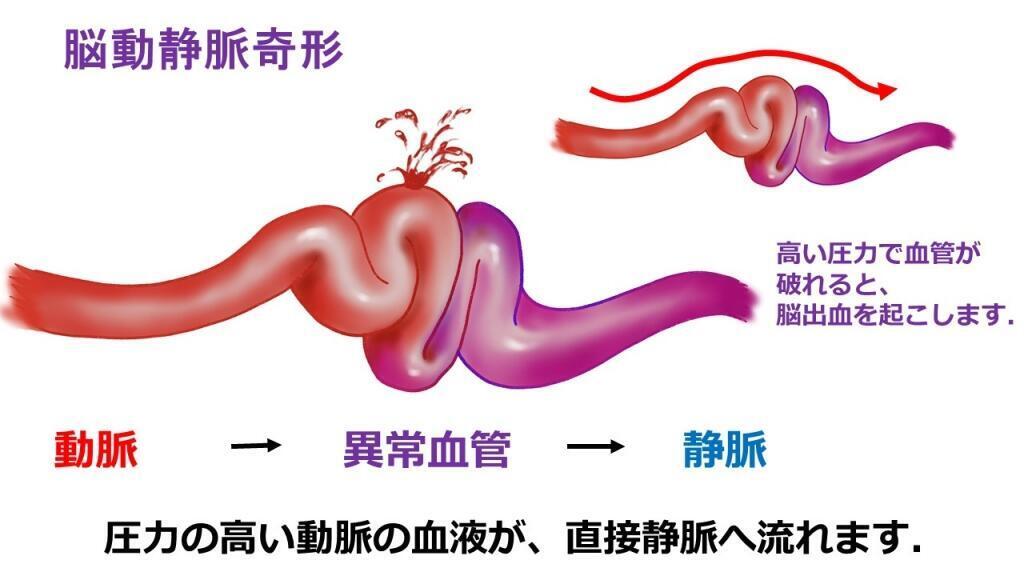

動脈から始まり、酸素を豊富に含んだ血液を高圧で心臓から他の器官に輸送する抵抗力のある血管です。それは小さな動脈に分岐し、次に毛細血管に分岐します。毛細血管は、動脈と静脈を接続する組織内の小さな血管です。

使用済みの血液は、酸素を含まず低圧のまま、動脈ほどの圧力に耐えられない細い血管である静脈を通って心臓に戻ります。したがって、毛細血管の主な機能は、動脈血が有毒な血液と「混合」するのを防ぐことです。

動静脈奇形がある場合、動脈は毛細血管を通さずに静脈と直接つながっているため、長時間動脈の血圧を支えることができず、静脈が破裂してしまいます。

この 2 つの間の異常な伝達はフィステルと呼ばれ、AVM 内に 1 つ以上存在する場合があります。